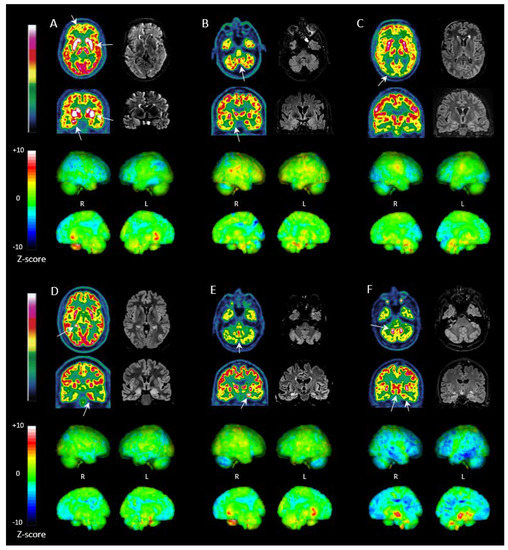

3.5. FDG PET in LGI1, NMDAR, GAD and CASPR2 Antibody Subtypes

3.6. Treated vs. Untreated Patients